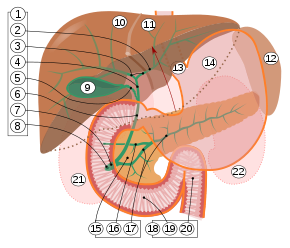

Anatomischer Aufbau

9. Gallenblase, 10–11. Linker und rechter Leberlappen. 12. Milz.

13. Speiseröhre. 14. Magen. 15. Bauchspeicheldrüse: 17. Ductus pancreaticus.

18. Dünndarm: 19. Zwölffingerdarm, 20. Jejunum

21–22: Nieren

Die menschliche Gallenblase ist normalerweise 8 bis 12 cm lang und 4 bis 5 cm breit. Ihre Form wird oft als „birnenförmig“ beschrieben. Die Gallenblase liegt in der Gallenblasengrube (Fossa vesicae biliaris) der Unterseite der Leber zwischen deren Lobus quadratum (quadratischer Lappen) und Lobus dexter (rechter Lappen) an, kann aber auch vom Gewebe der Leber umschlossen sein. Nach kaudal steht das Organ in Beziehung zur Flexura coli dextra, der rechten Biegung des Dickdarms (Colon), was bei Entzündungen zu Verwachsungen zwischen den beiden Organen führen kann, oder auch zu Verbindungen zwischen den jeweiligen Hohlräumen (biliodigestive Fistel). Dorsal (rückenwärts) befindet sich die Gallenblase nach medial in unmittelbarer Nähe der Pars superior des Zwölffingerdarms (Duodenum).[2] Bei den Schlangen liegt die Gallenblase hinter der Leber und relativ weit von dieser entfernt.

Das Organ kann in einen Fundus vesicae biliaris (Gallenblasenboden), Corpus vesicae biliaris (Gallenblasenkörper) und Collum vesicae biliaris (Gallenblasenhals) gegliedert werden.[2] Der Hals der Gallenblase, wo das Organ in den Ductus cysticus (Gallenblasengang) übergeht, besitzt eine spiralförmige Schleimhautfalte (Plica spiralis, auch Heister-Klappe), die eine Verschlussfunktion vor allem bei der Erhöhung des intraabdominalen Drucks z. B. beim Stuhlgang) wahrnimmt. Der Ductus cysticus vereint sich mit dem Ductus hepaticus communis zum Ductus choledochus, der im Ligamentum hepatoduodenale verläuft und in den Zwölffingerdarm mündet.[3]